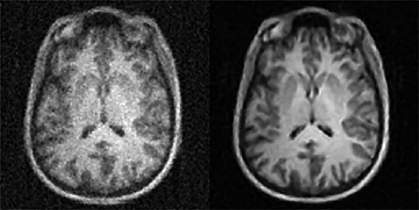

The team then tested how well AUTOMAP could reconstruct data using a clinical, real-world MRI machine and a healthy volunteer. They found that AUTOMAP enabled better images with less noise than the conventional MRI. The signal-to-noise ratio was better for AUTOMAP than conventional reconstruction (21.6 vs. 17.6). AUTOMAP also performed better on a statistical measure of error known as root-mean-squared-error (6.7% versus 10.8%). In addition, AUTOMAP was faster than the manual tweaking now done by MRI experts.